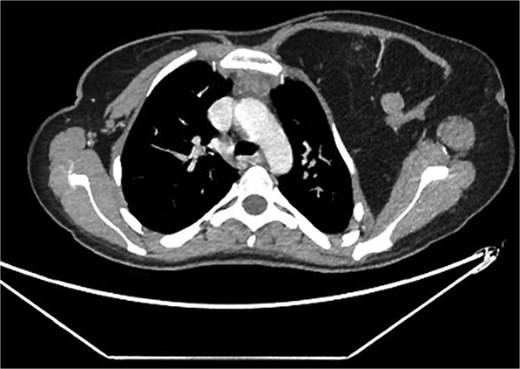

A 22-year-old female presented with progressive swelling in the left anterior chest wall above the left breast, associated with needle-like chest pain, left upper limb tingling, and weakness. The patient had a history of childhood cystic hygroma in the left axilla, previously excised. She denied constitutional symptoms but reported compressive symptoms such as shortness of breath, dysphagia, and hoarseness. A family history of breast cancer with thyroid metastasis was noted in her mother. On examination, the patient exhibited multiple bilateral solitary thyroid nodules and a bulky swelling in the left anterior chest and axilla. Computed tomography (CT) imaging (Fig. 1) revealed hypodense bilateral thyroid nodules, with magnetic resonance imaging (MRI) (Fig. 2) showing an enhancing left axillary lesion (2 cm, previously 1 cm) and an anterior chest wall lesion (1 cm). The mass, measuring 23 × 8 cm, extended to the lower left neck, left chest wall, and left axilla, encasing the neurovascular bundle without muscle or osseous invasion (Fig. 3). Fine-needle aspiration (FNA) cytology (Fig. 4) of the right thyroid nodule indicated atypia of undetermined significance (Bethesda III), while left-sided nodules and biopsies from the axilla, breast, and neck confirmed benign mature adipose tissue. The patient underwent total thyroidectomy, level V left neck exploration, and excision of lipomatous masses from the axilla, anterior chest, and breast, involving multiple surgical teams. Intraoperatively, vocal cords were preserved, and clear planes for lipoma excision were identified. The total excised lipomatous tissue weighed 13.57 kg (Fig. 5). Pathological examination confirmed mature adipose proliferation with no malignancy. Fluorescence in situ hybridization (FISH) ruled out MDM2 amplification, and genetic testing returned negative. Postoperatively, the patient developed deep vein thrombosis (DVT) in the left upper limb, diagnosed via Doppler study, and was treated with low-molecular-weight heparin (LMWH) followed by rivaroxaban. Follow-up MRI at 2 days and 3 months confirmed no residual or recurrent tissue growth. The patient started levothyroxine for thyroid function management and monitored for optimal dosing.

Interval increase in size of the large left upper lateral cervical, sub-pectoral, and axillary region fatty lesion protruding beyond the pectoralis major muscle into the upper breast region, keeping with lipomatosis.

Left chest wall lipomatosis with extension to the left neck and left axilla with thin septations, and there is a small enhancing focus (within the fatty lesion) which could be a small enhancing nodule or lymph node. The overall measurement has relatively increased (consider patient maturation).

Partially scanned left thoracic lipomatosis extending to the lower neck with mild mass effect over the left internal jugular vein. A multilocular goiter with a complex thyroid nodule is noted in the lower neck.